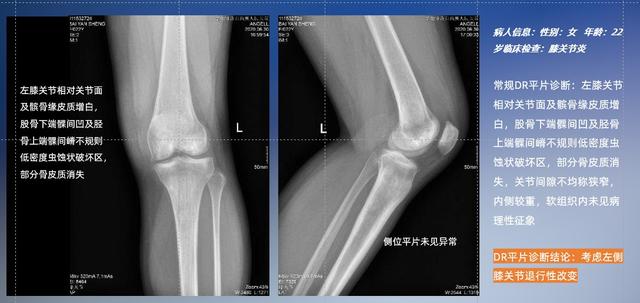

以膝关节疾病检查为例,膝关节在解剖学意义上是一种较为复杂的最大关节,由胫骨上端、股骨下端及髌骨组成。在股骨与胫骨的关节面之间存在两块半月板,分别处于内侧、外侧。膝关节的运动主要为伸、屈,在半屈位时可进行小幅度的旋外、旋内运动。随着现代人们体育生活以及肥胖的增加,膝关节疾病出现高发趋势,特别是关节磨损、膝关节炎与骨关节炎等关节退行性改变,长时间的内翻负荷会造成内侧关节软骨、骨性关节面的磨损。目前针对此类疾病的检查主要为平片下的负重位检查、CT检查以及MRI检查,相较于非负重位检查,负重位检查能更加真实反映膝关节结构中胫骨、股骨、髌骨实际对位关系和关节面的形态特征及关节间隙大小,对膝关节骨关节病诊断准确率高。

普通平片扫描与WR-3D扫描前后诊断结果对比

在负重位状态下,数字化X线三维扫描与重建,能够更好的呈现受检者关节受力改变的状态。388vip太阳集团科技创新的WR-3D动态三维影像重建系统,通过数字化X线摄影完成三维扫描并重建三维影像信息,包括断层图像重建、MPR多平面重建、MIP重建以及VR体绘制。其扫描时间短,剂量相较于CT设备大幅缩减,同时成本更低,在临床诊断以及医疗方案制定中具有极大的价值意义。而相较于普通平片下的负重位扫描,负重位动态三维影像重建技术能够避免二维状态下的组织结构重叠、密度分辨率不足、组织解剖结构难以分辨等问题。WR-3D支持多角度的三维观察,能全面的呈现被检查部位在多个角度下的三维影像信息,极大的降低了二维负重位检查带来的漏诊率。